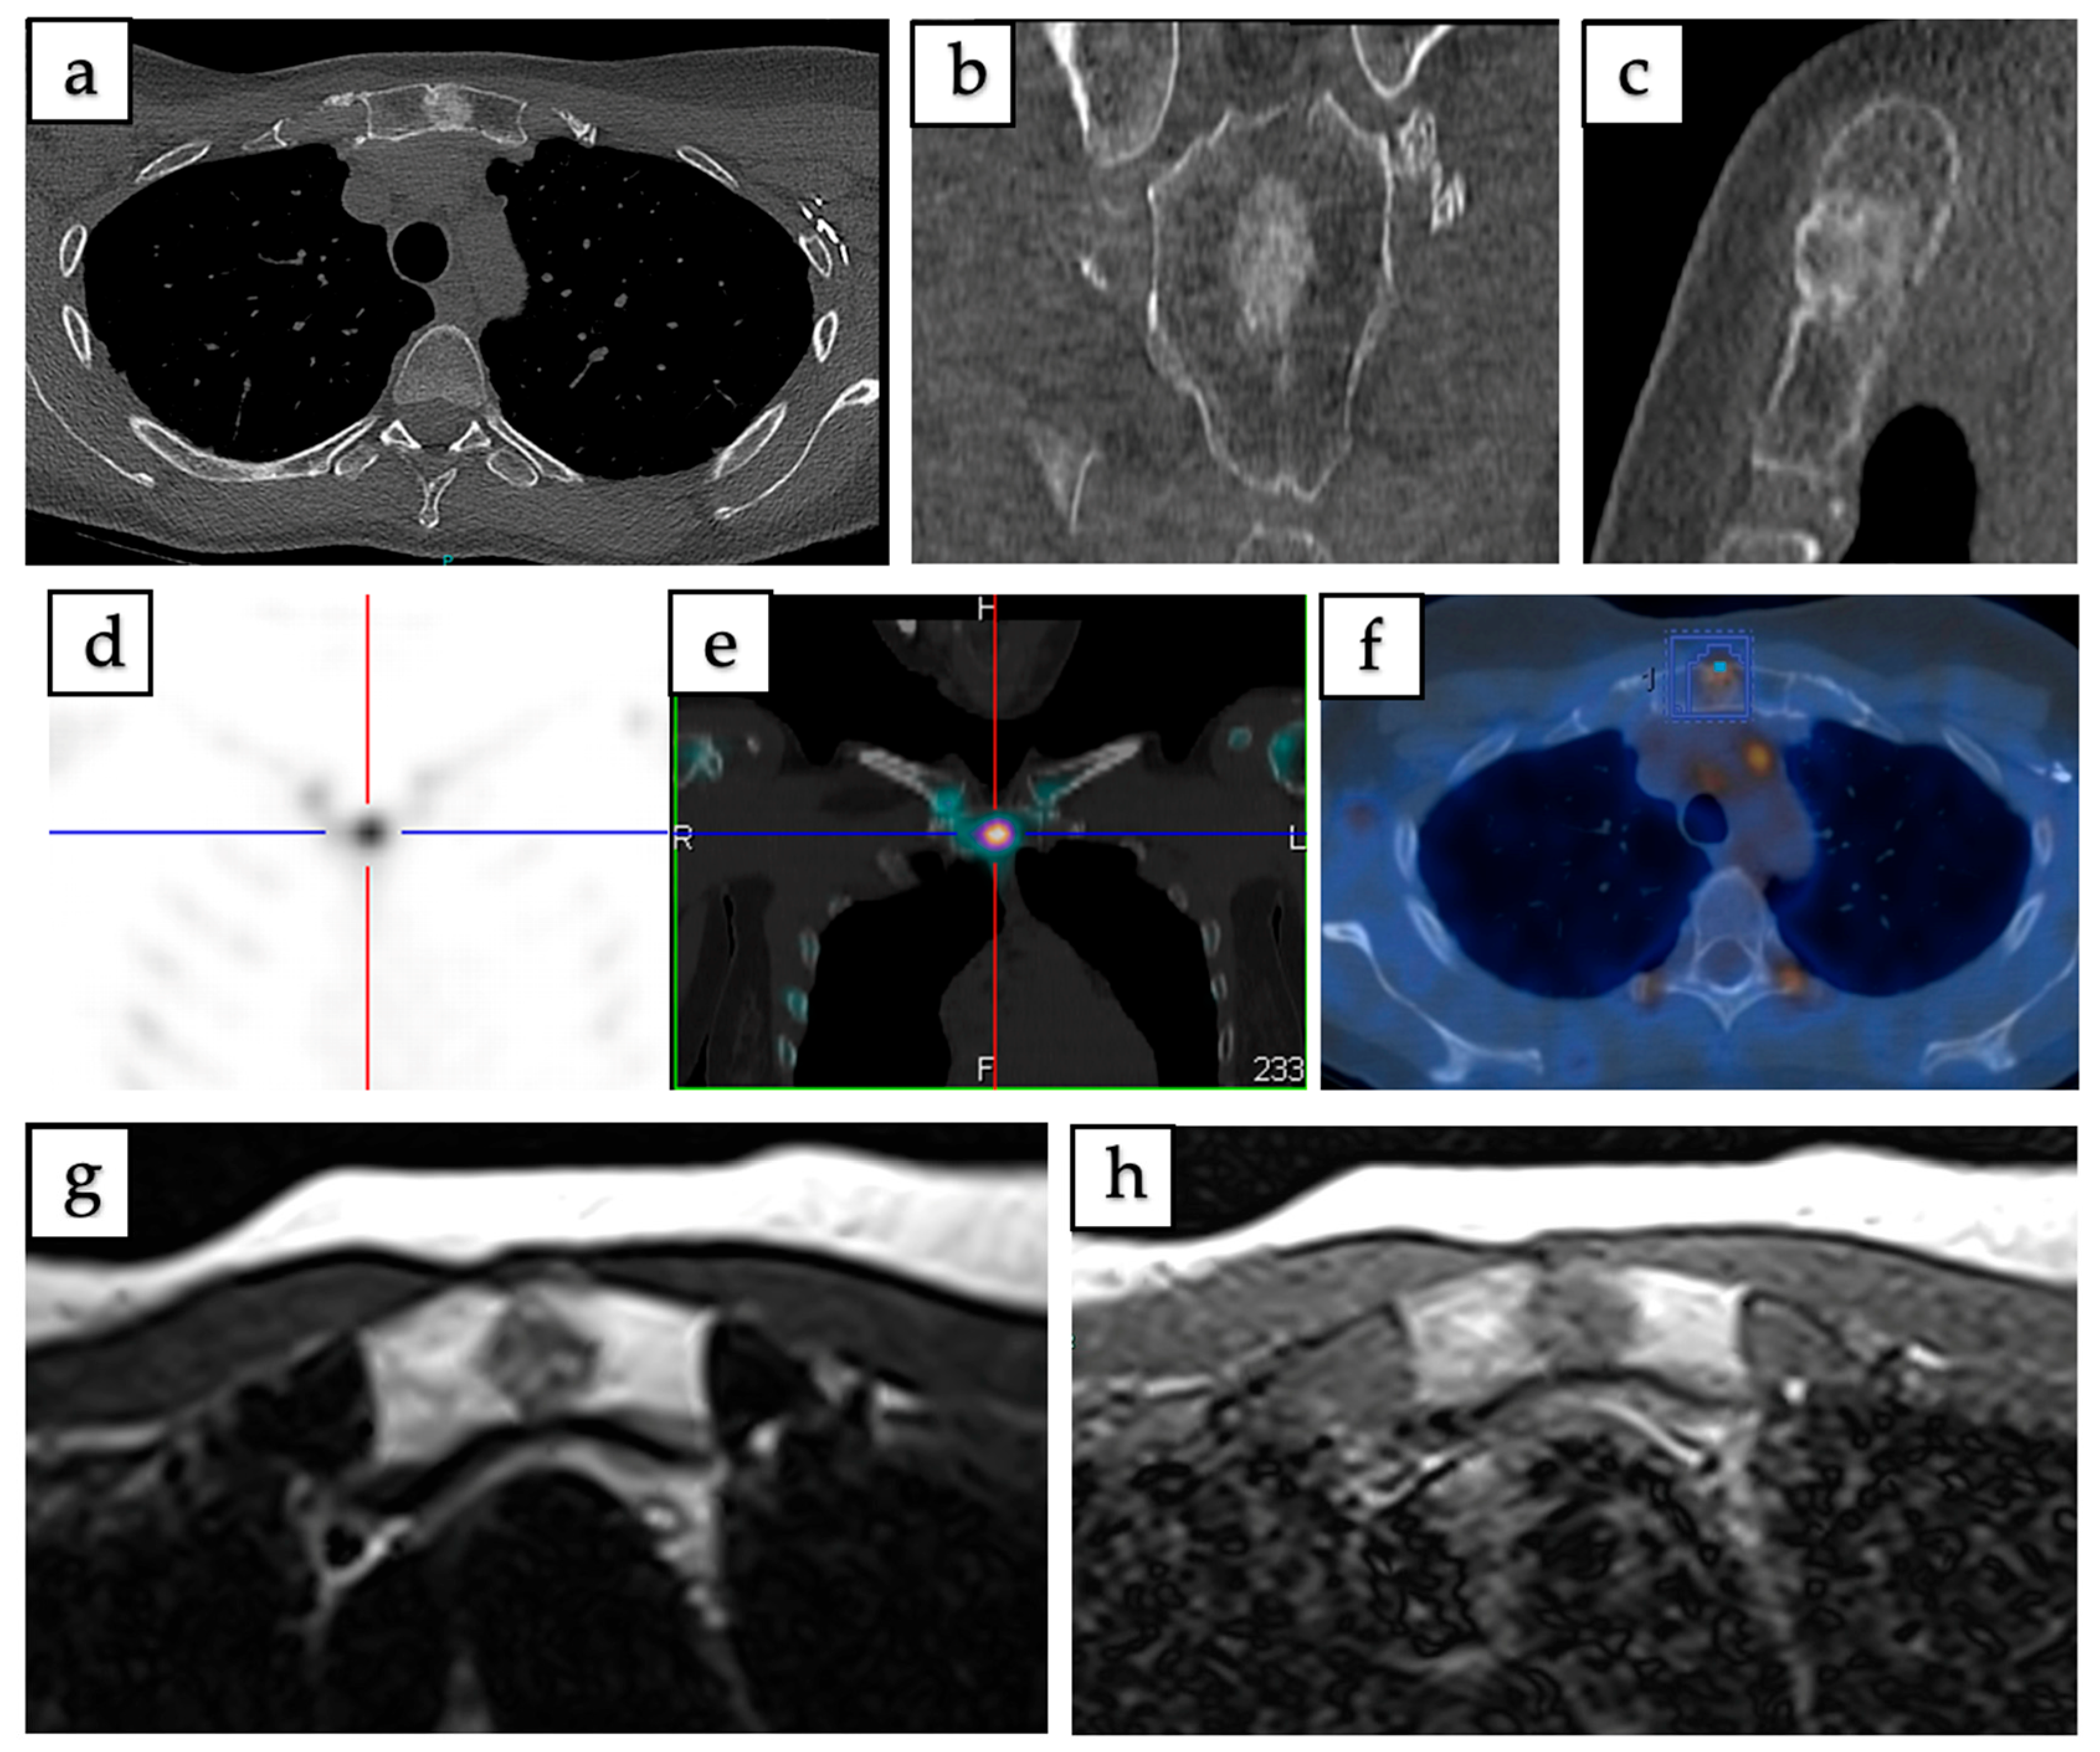

| Samargandi et al., 2023 [6] | France | Case Report | 2 | Manubrium sterni, left iliac bone | Incidentally found during breast cancer staging, incidental bony lesion on MRI | CT, MRI, 18F-FDG PET/CT, Bone scintigraphy/SPECT |

| Stolte et al., 2023 [11] | Switzerland | Case Report | 1 | Upper left pubic bone (pelvis) | Lesion discovered incidentally on 18F-FDG PET/CT during lung cancer staging | CT, 18F-FDG PET/CT |

| Mi-Kyung Um et al., 2020 [32] | South Korea | Case Report | 1 | T7 vertebral body (spine) | Discovered incidentally on chest CT during tuberculosis screening | CT, MRI, 18F-FDG PET/CT |